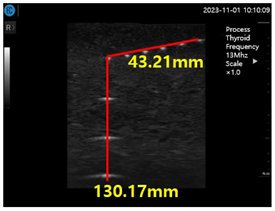

Figure 15a shows ultrasonic gel testing at various time intervals using the ATS-539 phantom. Figure 15b shows the sharpness of the image of the manufactured gelatin soft gel after storing it in alcohol and performing a sharpness test at 1 h intervals for 72 h. The results are presented in Figure 15b. In this paper, the experiment using a soft solid gel did not require IRB agreement. This research on the proposed gelatin soft solid gel showed its functionality to be better than that of ultrasonic gel, including on grayscale, echo, and color. This means that it can overcome the tissue density dead zone to increase high resolution performance. To help imaging accuracy, it is proven that gelatin soft gel, especially the soft solid gel, can replace ultrasonic gel to simplify disinfection and ensure permanent use. Image corrosion testing of gelatin soft solid gel for 30 min is shown in Figure 16a. Ultrasonic gels were tested at different times using an ATS-539 phantom, where the gel was soaked in ethanol for 72 h, as shown in Figure 16b. Afterwards, the gel’s condition was tested again. Finally, Figure 16c measures the imaging resolution of the gelatin soft tissue gel.